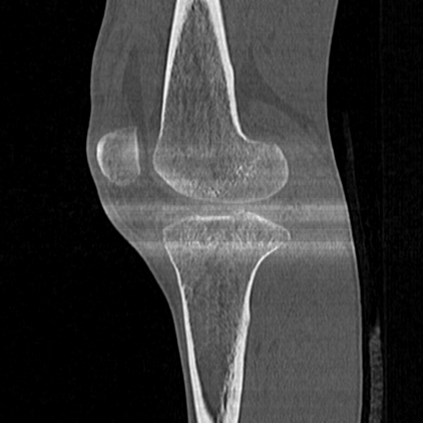

CT reconstruction provides radiologists with images for diagnosis and treatment, yet current deep learning methods are typically limited to specific anatomies and datasets, hindering generalization ability to unseen anatomies and lesions. To address this, we introduce the Multi-Organ medical image REconstruction (MORE) dataset, comprising CT scans across 9 diverse anatomies with 15 lesion types. This dataset serves two key purposes: (1) enabling robust training of deep learning models on extensive, heterogeneous data, and (2) facilitating rigorous evaluation of model generalization for CT reconstruction. We further establish a strong baseline solution that outperforms prior approaches under these challenging conditions. Our results demonstrate that: (1) a comprehensive dataset helps improve the generalization capability of models, and (2) optimization-based methods offer enhanced robustness for unseen anatomies. The MORE dataset is freely accessible under CC-BY-NC 4.0 at our project page https://more-med.github.io/